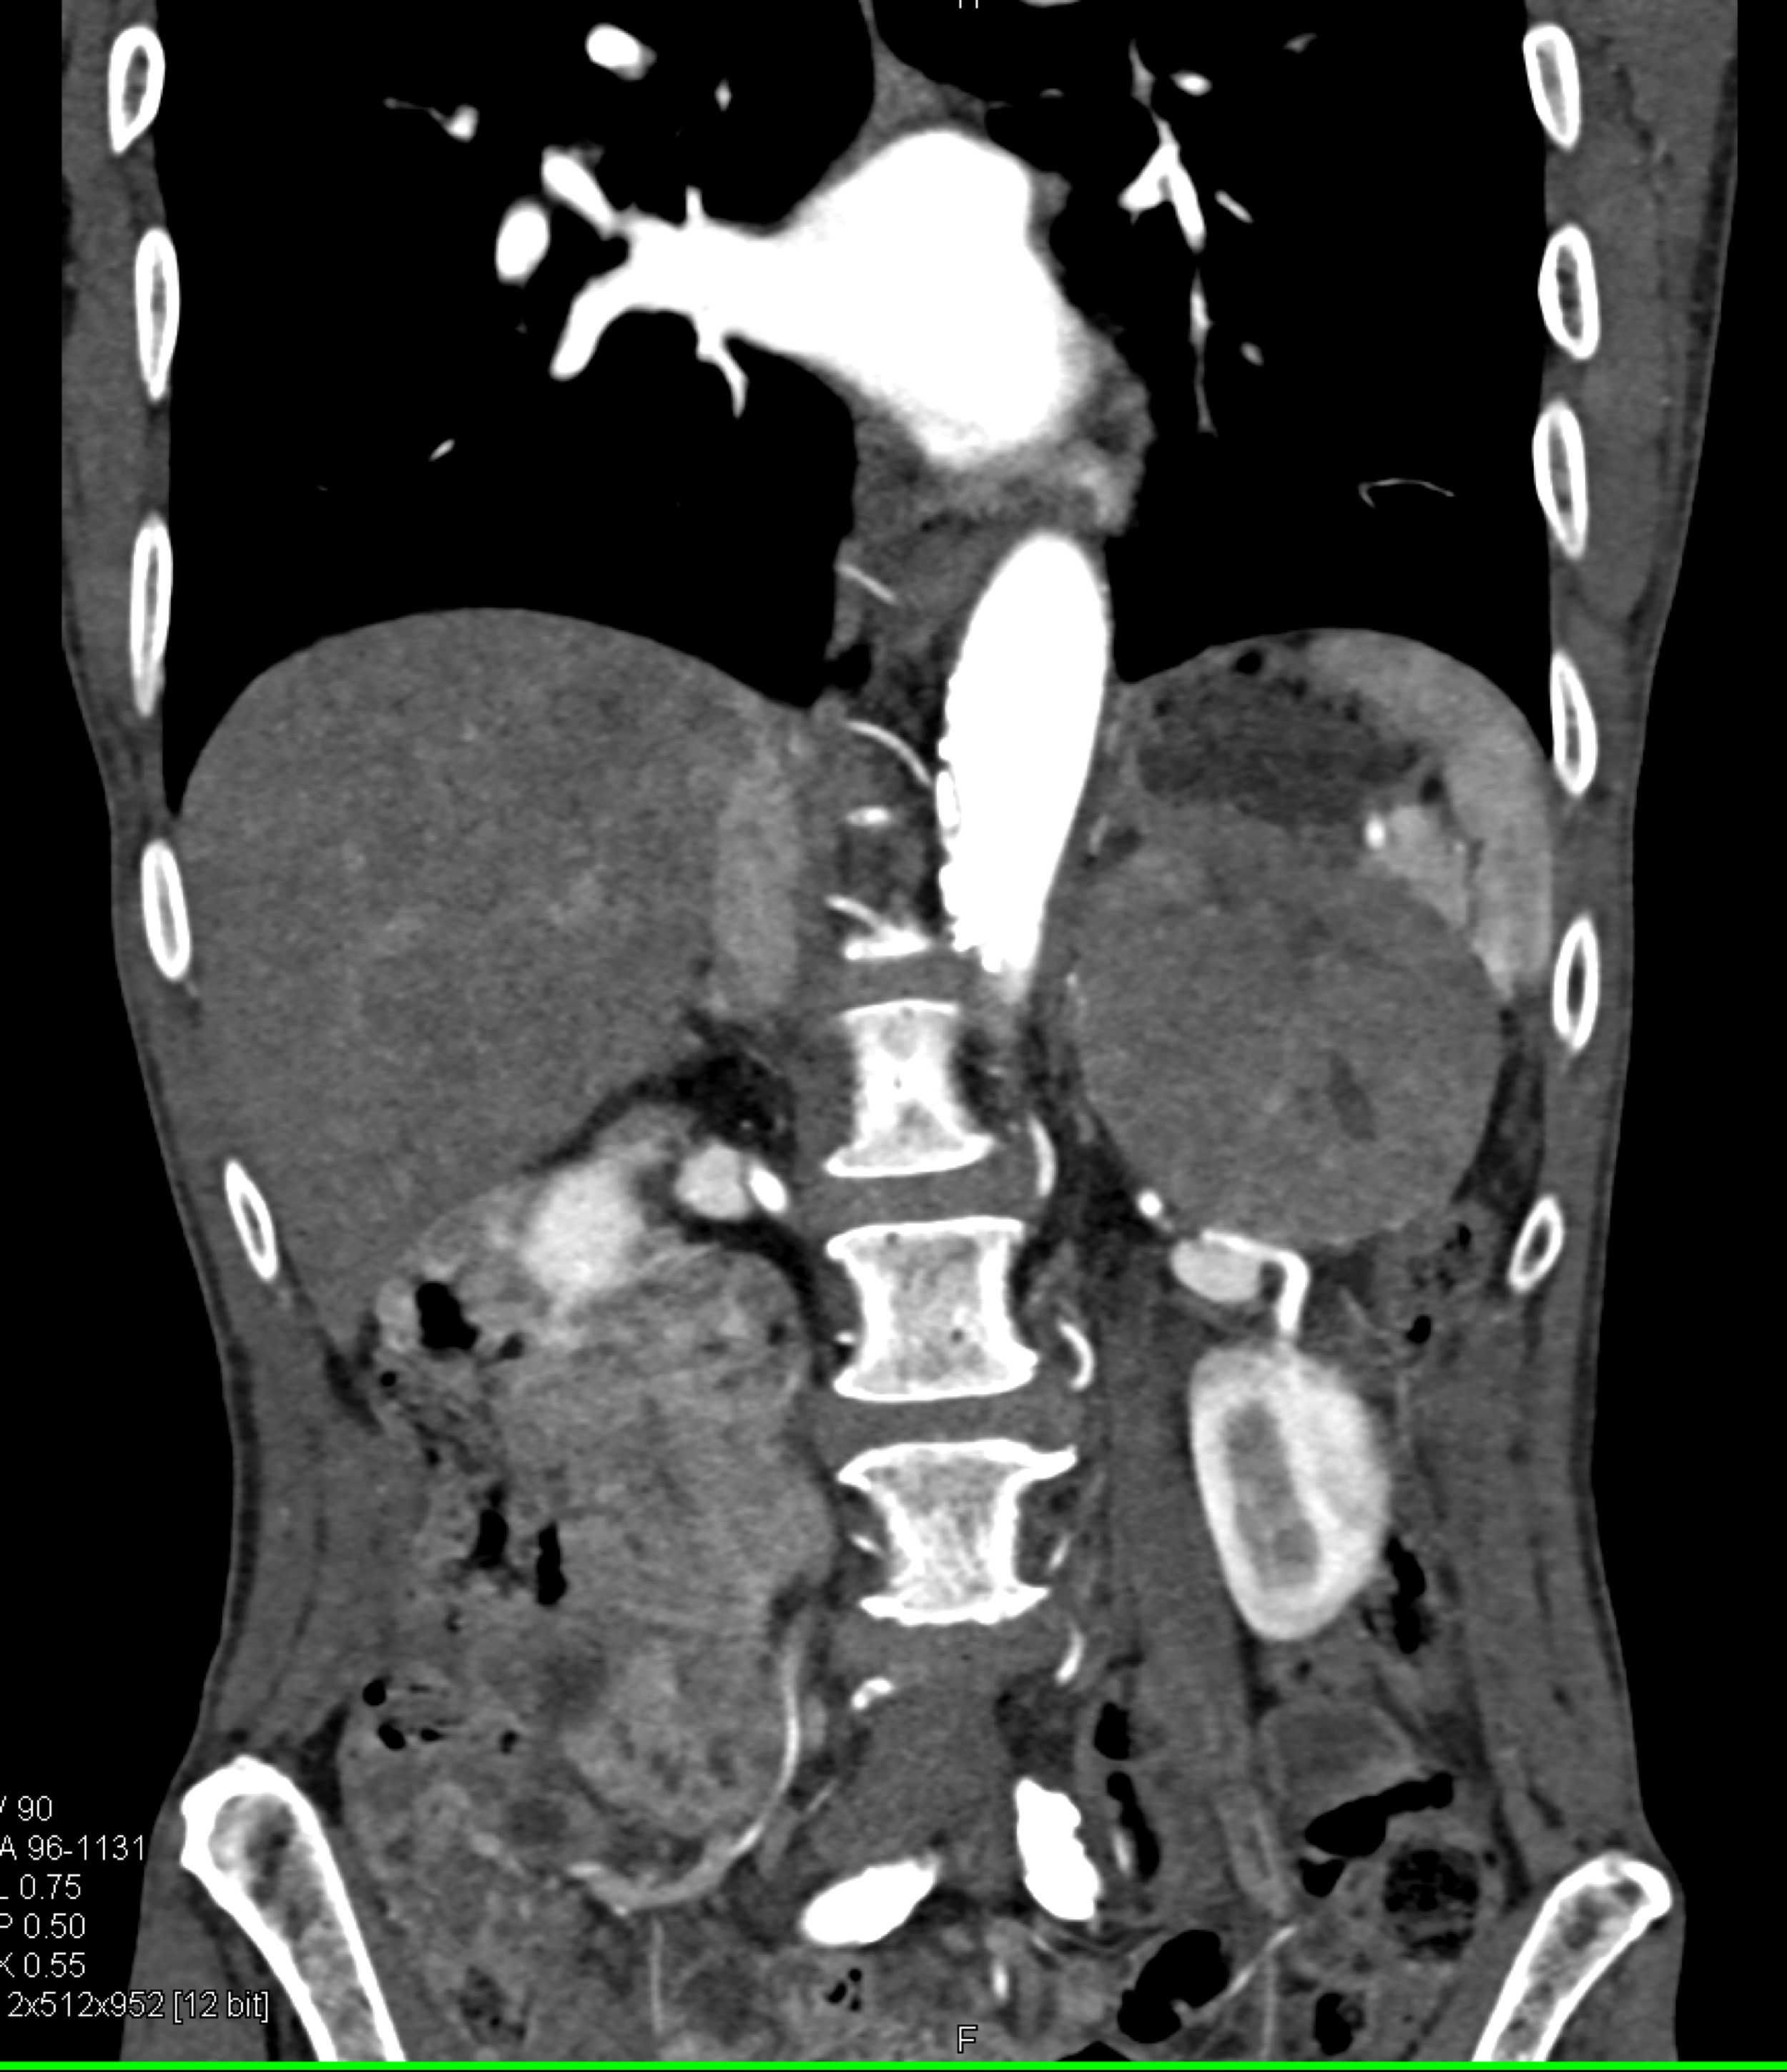

9) The most likely diagnosis is?

primary adrenal carcinoma

hepatoma with adrenal metastases

pheochromocytoma

adrenal hematoma